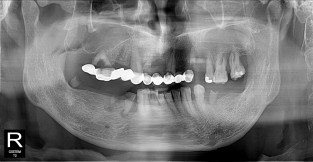

• 2

전체어금니

치료기간 : 2021-11-08 ~ 2022-12-22

1. 상기 x-ray 이미지 모두 동일한 해당 의료기관에서 진료한 환자입니다.

2. 상기 x-ray 이미지 모두 동일 인물의 것입니다.

3. 치료 전 이미지는 2021-11-08에 촬영했으며, 치료 후 이미지는 2022-12-22에 촬영하였습니다.

4. 상기 x-ray 이미지 모두 동일 조건에서 환자분의 동의를 받아촬영되었습니다.

* 임플란트 시술은 환자분의 상태(고혈압, 당뇨 등)에 따라 부작용이 있을 수 있으니, 반드시 전문의와 상담이 필요합니다.

* 임플란트 수술 부작용

: 수술 후 출혈, 교합, 통증, 붓기, 염증 등의 문제점이 발생할 수 있습니다.)